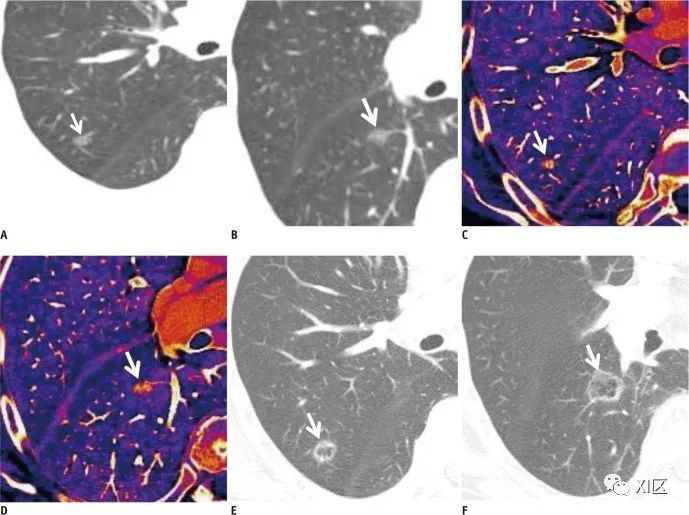

三物质分解算法能够生成肺血容量(PBV)图,该图表示碘在肺实质中的分布;它可以作为肺灌注的指标。PBV图和碘图有助于识别肺栓塞相关的灌注缺陷(图13)。此外,由于碘图显示肺结节的血供,有助于描述结节的特征(图14)。

图14 78岁女性,右上下叶肺腺癌新发肺转移瘤表现为磨玻璃样阴影结节(部分为实性)。A、B 从双能CT获得的增强加权平均图像显示右肺中新形成的10 mm(A)和12 mm(B)大小的磨玻璃样阴影结节(箭头)。在RECIST 1.1版本中,磨玻璃样阴影结节是未明确定义的病变。因此,肿瘤反应被评估为稳定的疾病。C、D 这些结节在双能CT彩色编码碘增强图像上显示明显增强(C为58 HU,D为89 HU)(箭头)。因此,肿瘤反应被评估为进展性疾病。E、F 进一步随访CT扫描(双能CT扫描两个月后)的常规图像显示结节大小显著增加,出现内部新的空洞(箭头),提示空洞转移。肿瘤反应再次被确认为进展性疾病。碘图上病灶与实质的对比度更好,可以提高病灶的清晰度和病灶边缘的描绘,从而有助于可靠地识别小病灶或仅轻微强化的肿瘤。这些图像还有助于区分增强组织、非增强组织和伪增强组织。双能CT碘定量图像有助于估算组织中的碘浓度(mg/ml)。